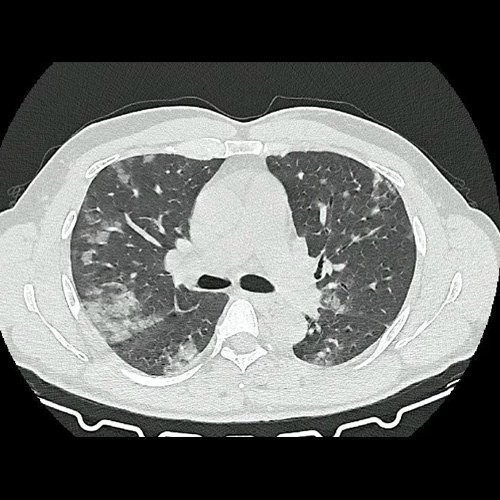

• Tomografía de tórax sin contraste endovenoso (Dia 0):Se observan múltiples áreas de consolidación parenquimatosa con broncograma aéreo y de distribución difusa por ambos pulmones, predominando en los lóbulos inferiores, asociadas a engrosamiento de los septos y rodeadas de tenue vidrio esmerilado. Se identifican estructuras ganglionares lateroaórticas, pretraqueales y subcarinales, ninguna de ellas sin alcanzar rango megálico.

Tomografia de torax sin contraste endovenosos (Ventana pulmonar-corte axial)